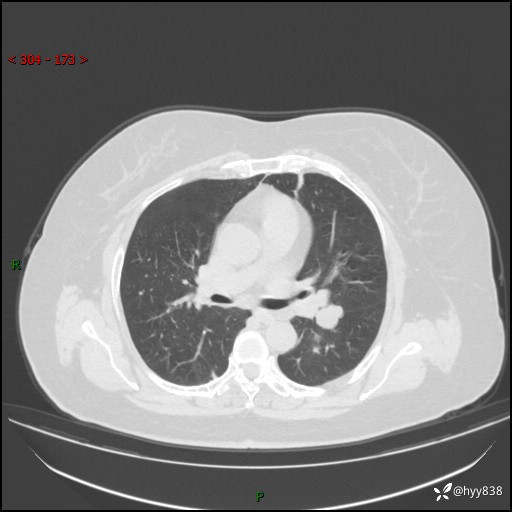

主诉:检查发现左上肺结节8年,较前增大。

简要病史:患者于8年前体检行胸部CT检查发现左上肺结节(4mm),患者平素间断咳嗽咳痰,无心慌、胸闷、胸痛、呼吸困难、低热、盗汗,无头痛、头晕,无腹痛、腹胀等不适,未行特殊处理,定期复查。2023-09-21胸部CT示左上肺结节(2cm)较前增大,2024-02-01胸部CT示左上肺尖后段(39*32mm),左侧肺门及纵隔淋巴结增大,现患者欲求手术治疗,遂来我院就诊,以“左上肺结节”收入我科。 患者自起病以来,精神可,睡眠可,饮食可,大小便正常,体重无明显改变。

胸部CT平扫